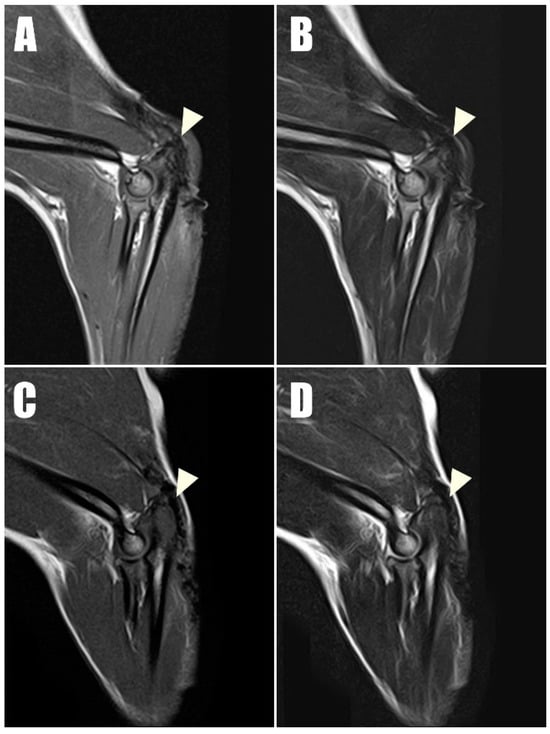

Figure 8. Postoperative magnetic resonance imaging (MRI) taken one year postoperatively captured (A) T1-weighted and (B) T2-weighted sagittal images of the right triceps brachii tendon, along with (C) T1- T1-weighted and (D) T2-weighted sagittal images of the left of triceps brachii tendon. These images demonstrate low signal intensity on both T1 and T2 sequences, indicating intact connectivity of the tendon.

Radiography (Figure 6C,D) and ultrasonography (Figure 7C,D) six months postoperatively confirmed that the transverse hole of the right side healed without any complications, and the bilateral triceps brachii tendons were well-maintained and attached to the olecranon, with no specific changes in internal echogenicity or echotexture. MRI (Figure 8) showed mild inflammatory changes near the suture knot and fibrotic scar tissue within the tendon but confirmed firm attachment of the tendon to the olecranon. Three years following the surgery, the patient exhibited no signs of functional loss (Video S2) or pain, confirming the long-term success of the treatment. The owner expressed satisfaction with the clinical outcomes.

Tendon structural integrity and musculotendinous change are best evaluated by magnetic resonance imaging (MRI). In the late stages of tendon healing, tendons typically exhibit low signal intensity across T1- and T2-weighted MRI sequences [23]. In the current case, the bilateral triceps brachii tendons at their attachment to the olecranon demonstrated low signal intensity in all sequences at the one-year postoperative evaluation, with the exception of mild inflammatory changes observed near the suture knots and surrounding scar tissues.